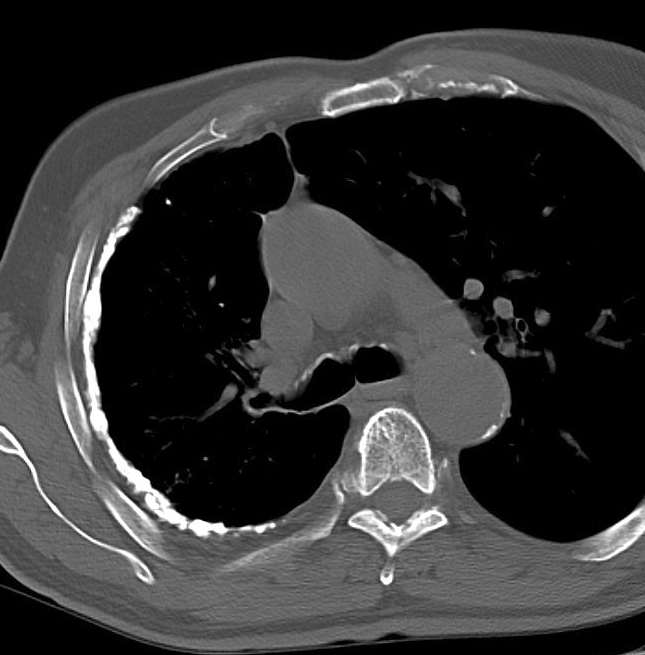

Gallery Pleural old TB CT

old TB CT